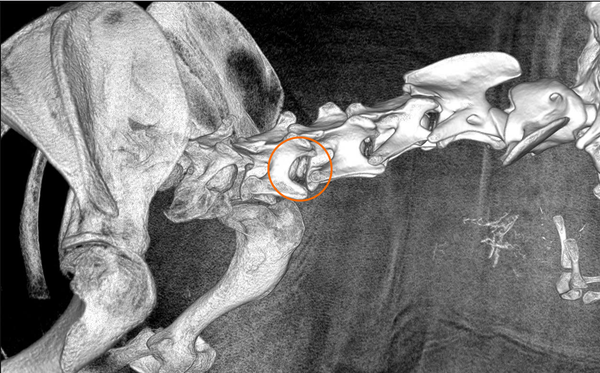

Hình ảnh chụp CT-scan sau phẫu thuật

Kết quả sau phẫu thuật

Chỉ sau vài ngày, chức năng vận động của Maxi đã cải thiện rõ rệt, cho thấy tủy sống và dây thần kinh được giải phóng thành công.

Đây là một dấu hiệu phục hồi tích cực, khẳng định hiệu quả của phẫu thuật thoát vị đĩa đệm ở chó khi được thực hiện đúng kỹ thuật và kịp thời.